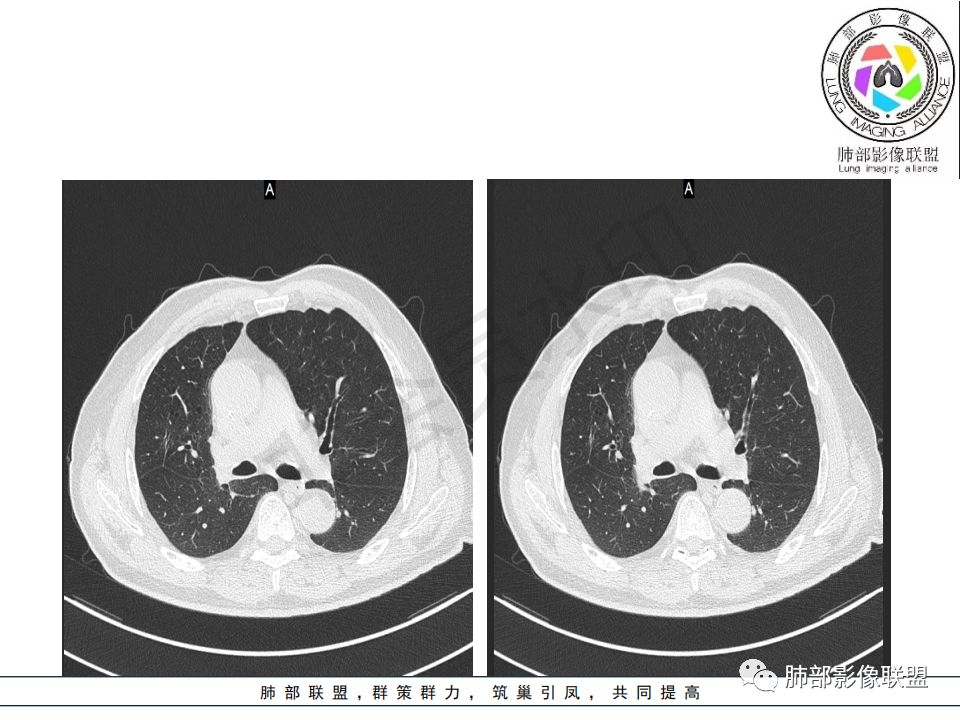

病史:男.77岁,咳嗽1月;干咳,少许白痰,无发热,2013胃癌术后,角蛋白24.65(0-3.07),SCC和proGRP不高;

影像:影像右侧大支气管阻塞,临床没有症状或很轻微,要想到胃腺癌转移;胸壁代偿好,透亮度稍低不明显,慢性过程;34.8-52.5HU,主病灶支气管前壁另有1结节,都做成增强两期了,动脉期较平扫有强化;

诊断:多发,转移,无淋巴结及胸腔积液;

鉴别:原发鳞癌。

晨读:患者老年男性,以咳嗽一月就诊,少量白痰,胸CT:纵隔右移,右肺体积缩小,气管下段管壁可见结节样改变,气管软骨变形,气管下段及右主支气管可见新生物向管壁浸润,并向管腔外生长,右上肺肺不张,但不张边缘可见病灶呈膨胀性生长,可见分叶,增强后强化明显。考虑:肺部恶性病变(鳞癌?)

1.右肺上叶较大块影,密度不均,轻度强化并见低密度区,所属支气管截断并腔内突入,是符合肺鳞癌的影像学特征和生物学行为的。